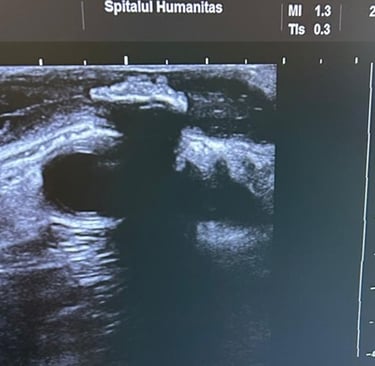

ECOGRAFIE

ecografie mamară

ecografie tiroidiană

puncție biopsie sân și ganglioni Tru-cat - pentru diagnosticul tumorilor maligne

puncție tiroidiană cu ac fin (FNAB) - pentru diagnosticul citologic al nodulilor tiroidieni

ecografii înainte și după chirurgia plastică (sân, perete abdominal, față)

Avantajele ecografiei intraoperatorii